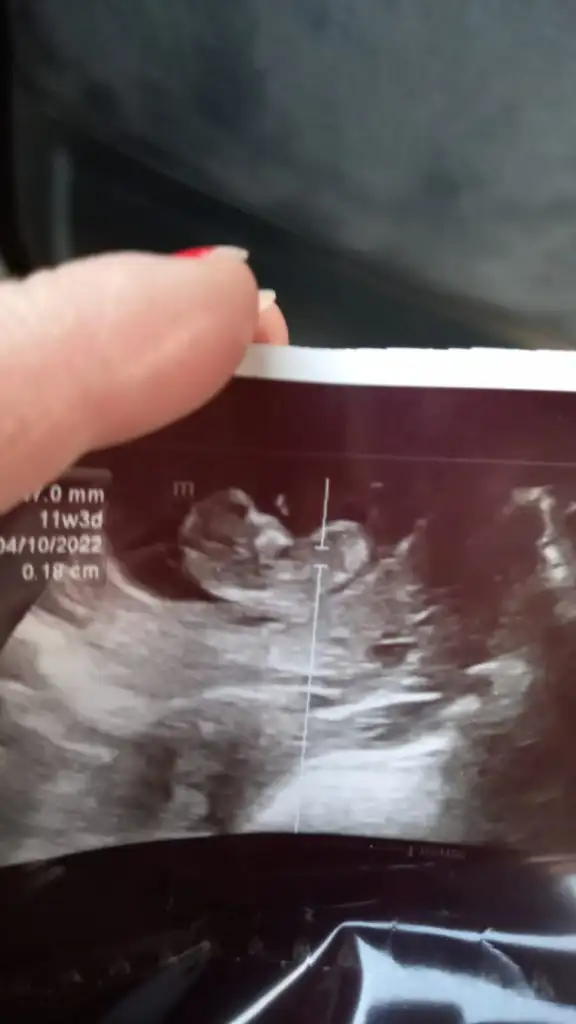

Kizlar eltimin bebegi suan 11. Hafta da

Nub belli ediyor mu cinsiyeti var mi tahminler